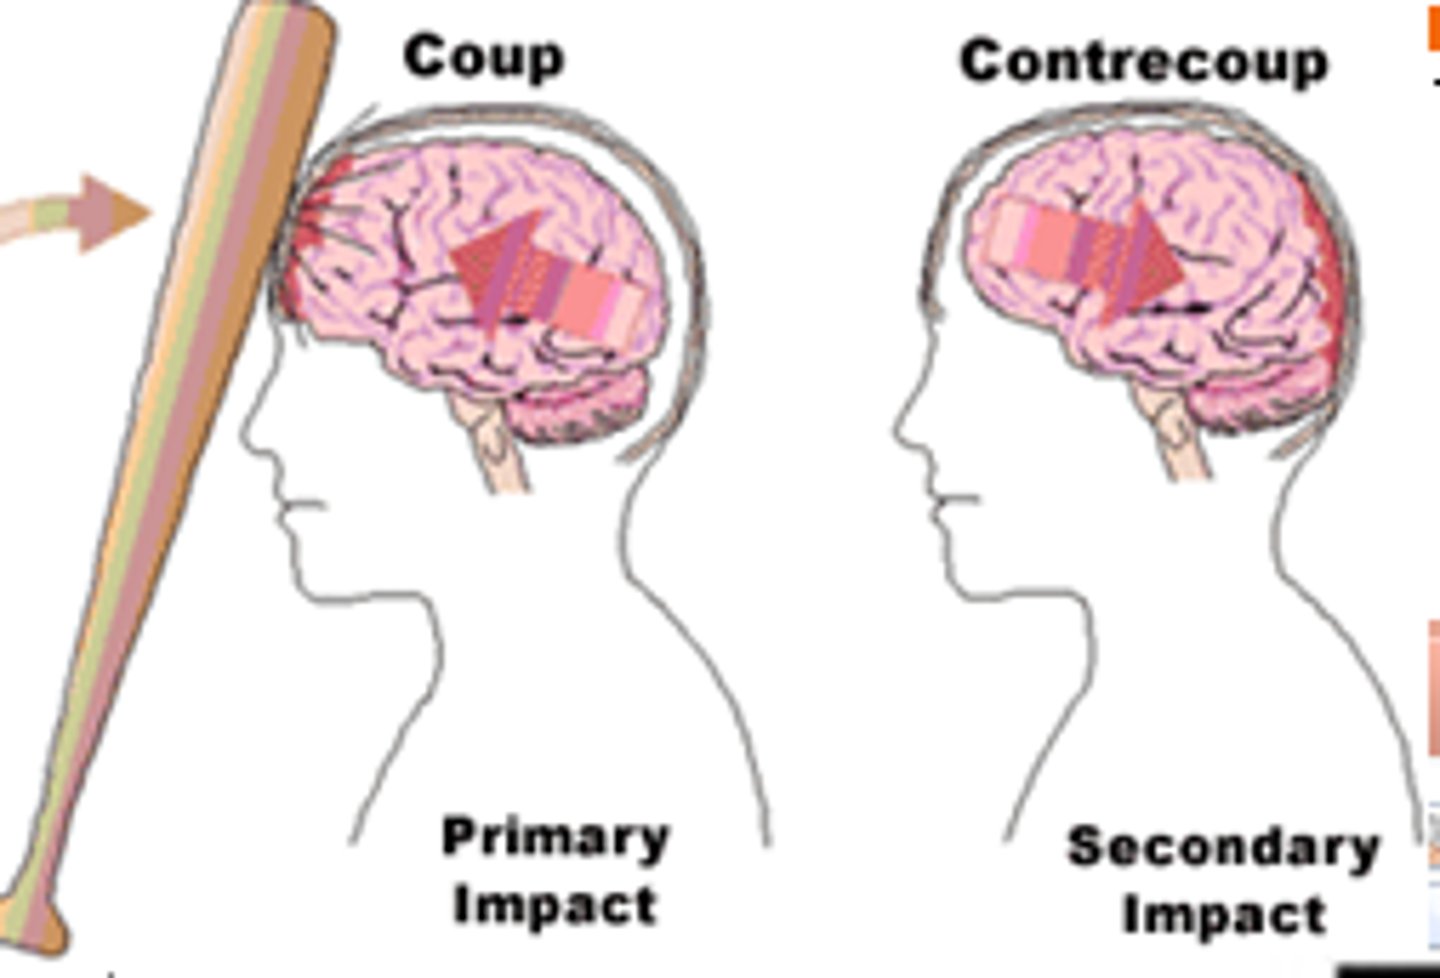

Traumatic brain injuries (head trauma)

1) a leading cause of accidental death in U.S.

2) Caused not only by localized injury at site of blow but also by ricocheting effect as brain hits opposite end of skull

Contusion

Bruising in the brain and can cause permanent Neurological Damage